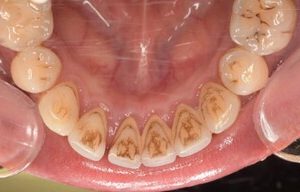

CASE 2

Before

After

基本情報

| 年齢・性別 | 30代・男性 |

| 主訴 | 歯石を取りたい |

| 治療内容 | 超音波スケーラーでの歯石除去 |

| 治療期間 | 60分 |

| 治療費 | 初診料を含め約4,500円 |

| リスク・副作用 | 歯ぐきに違和感や痛みを覚える場合がある。 1週間程度、歯を磨くといつもより出血することがある。 腫れていた歯ぐきが引き締まることで歯ぐきが下がった様に見える。 歯ぐきが下がることで歯がみしやすくなることがある。 一時的に歯の動揺(ゆれ)が増す場合がある。 |